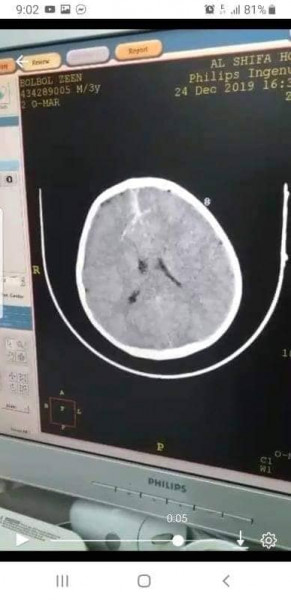

نجح الفريق الطبي برئاسة د. خميس الشيخ ديب استشاري جراحة المخ والأعصاب وبمشاركة د. عايش أبو وردة ، بإنقاذ حياة طفل يبلغ من العمر "10" سنوات وصل لقسم الطوارئ ، إثر تعرضه لسقوط من علو ما أدي إلي إصابته مباشرة "بسيخ "حديدي اخترق عظمة الجمجمة بطول "12" سم داخل الدماغ .

حيث أوضح د. الشيخ الديب أنه وفور وصول الطفل لقسم الطوارئ تم تحضير الطفل لعملية جراحية وبصورة عاجلة أدخل قسم العمليات حيث تم رفع السيخ وإيقاف النزيف ، فقد استمرت العملية لمدة ساعة ، ومن ثم نقل المريض لقسم العناية المركزة لمدة يوم كامل ليخرج بعدها بكامل وعيه ولايوجد أي مضاعفات أو مشاكل صحية علي الطفل وقد تم خروجه من القسم بعد إجراء الفحوصات الطبية والمخبرية والتأكد التام من سلامته .